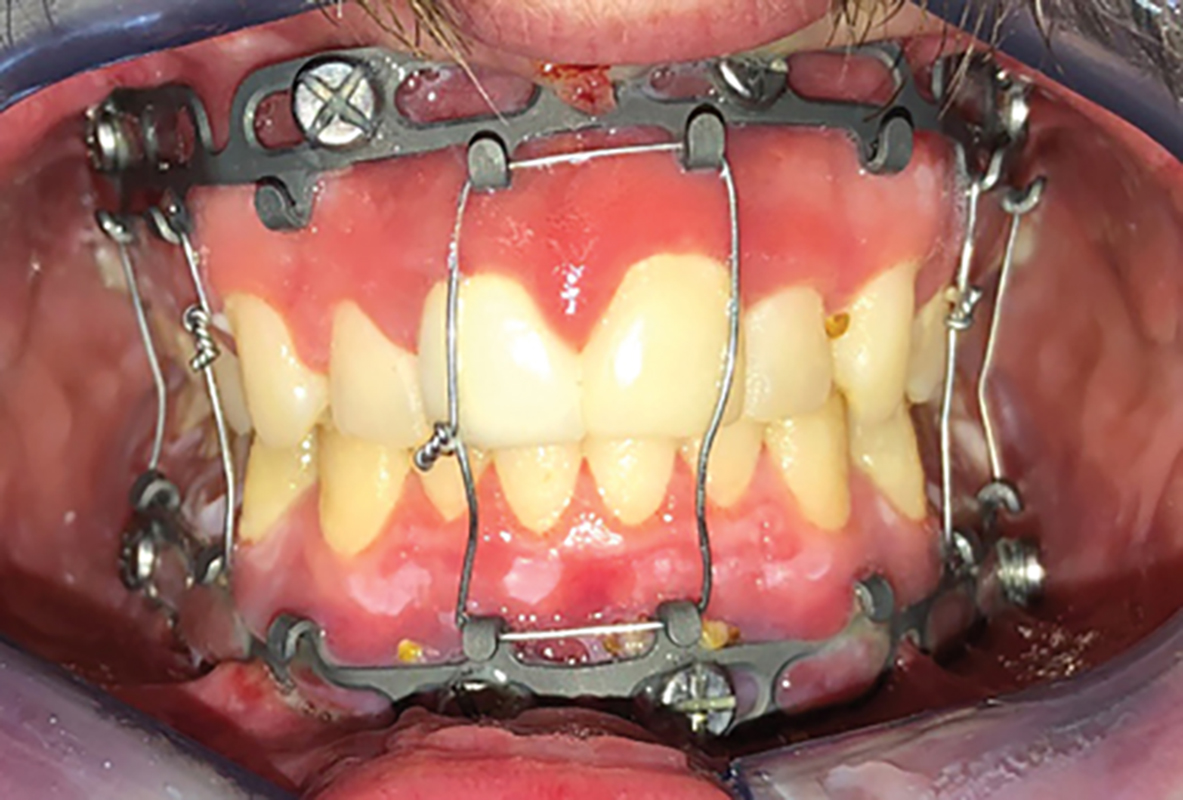

Management of Severe Obstructive Sleep Apnea With Maxillomandibular Advancement Surgery

Abstract Obstructive sleep apnea (OSA) is a common disorder that causes patients to temporarily stop or decrease their breathing repeatedly during sleep. OSA has been associated with increased morbidity and mortality rates as well as decreased quality-of-life. Certain patients with maxillomandibular abnormalities, such as mandibular retrognathia, suffer from moderate to severe OSA. Although continuous positive … Read more